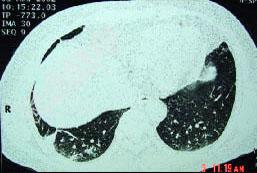

- 单项选择题男,32岁, 外出旅游1个月后,咳嗽1周, CT检查如图,最可能的诊断为 ( )